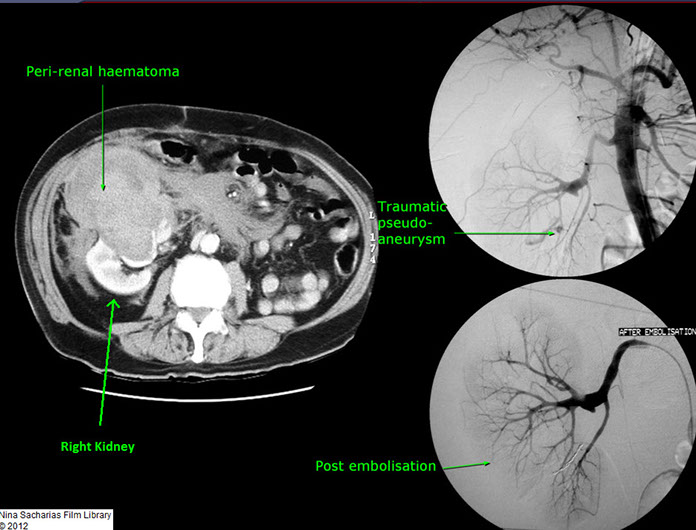

Control of bleeding by embolization.

Bleeding from a pelvic vessel resulting from a fracture, controlled by embolisation